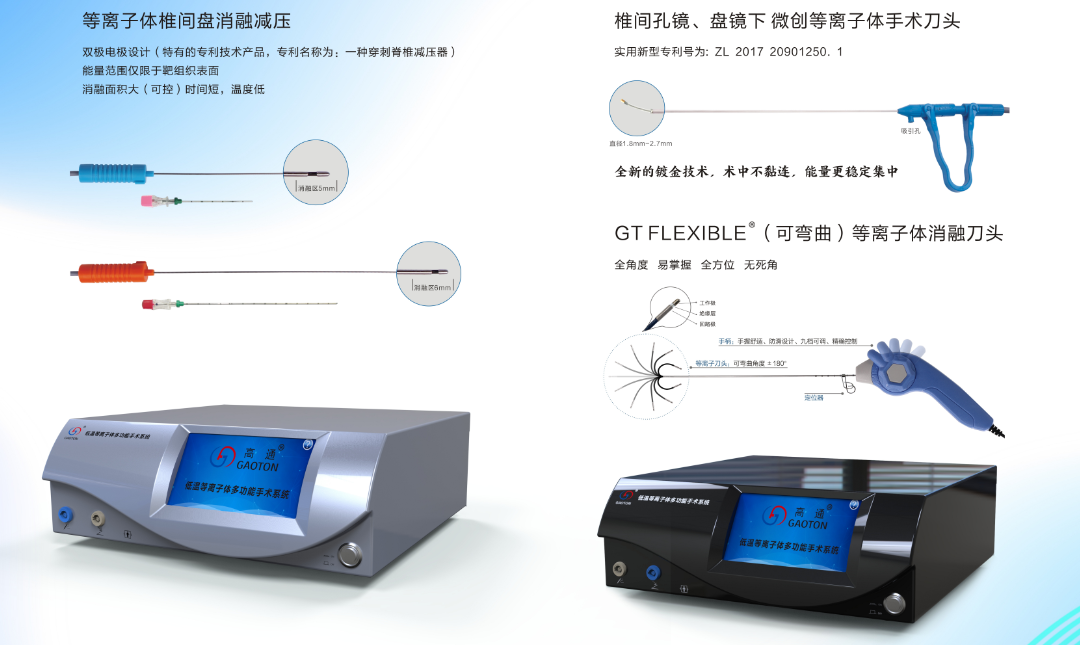

若采用手術治療的方式,需根據實際病情選擇手術方式。目前對于腰椎間盤突出癥,主要分為微創(chuàng)治療及傳統(tǒng)開放手術治療,一般在考慮到手術效果、恢復情況等因素下,當以微創(chuàng)療法為首選。而“低溫等離子體多功能手術系統(tǒng)”則是微創(chuàng)療法中的新貴。

等離子手術理論

手術適用范圍

1、靶點消融術、盤內汽化減壓術、神經阻滯術。

2、椎間孔鏡、椎間盤鏡下汽化、切割、消融、止血剝離術。

3、膝關節(jié)、肩關節(jié)、髖關節(jié)、小關節(jié)和腱性疾病等手術。

產品技術優(yōu)勢

1、40℃-70℃低溫下汽化消融。

2、靶點消融減壓效果立竿見影。

3、安全、微創(chuàng)、局麻手術。

4、不破壞纖維環(huán)的完整性。

5、術后恢復快。